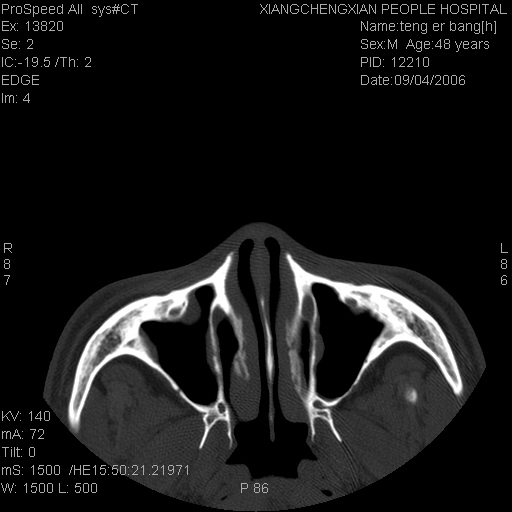

ct:平扫+冠扫:双侧鼻骨对比,冠扫s6#示右侧鼻骨尖部可见线状低密度影,边缘光滑,并见硬化.软组织未见肿胀.

诊断意见:鼻额缝(鼻骨与上颌骨额突缝),但个别同志认为是骨折.因此请同行们会诊.多谢了!

正常鼻颌缝。软组织无肿胀。鼻腔无积液积血。鼻骨光滑规整无中断。均不支持骨折。

正常的,双侧对称.边缘光整,且逢等宽.

正常鼻颌缝。软组织无肿胀。鼻腔无积液积血。鼻骨光滑规整双侧对称。均不支持骨折。